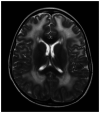

Figure 1-4.

Brain MRI with diffuse prolonged T2 signal seen in the deep and subcortical white matter through both cerebral hemispheres in a 10-year-old boy with merosin-deficient congenital muscular dystrophy.